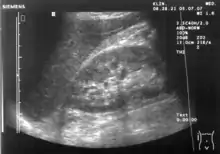

Abdominal ultrasonography (also called abdominal ultrasound imaging or abdominal sonography) is a form of medical ultrasonography (medical application of ultrasound technology) to visualise abdominal anatomical structures. It uses transmission and reflection of ultrasound waves to visualise internal organs through the abdominal wall (with the help of gel, which helps transmission of the sound waves). For this reason, the procedure is also called a transabdominal ultrasound, in contrast to endoscopic ultrasound, the latter combining ultrasound with endoscopy through visualize internal structures from within hollow organs.

Abdominal ultrasound can be used to diagnose abnormalities in various internal organs, such as the kidneys,[1] liver, gallbladder, pancreas, spleen and abdominal aorta. If Doppler ultrasonography is added, the blood flow inside blood vessels can be evaluated as well (for example, to look for renal artery stenosis). It is commonly used to examine the uterus and fetus during pregnancy; this is called obstetric ultrasonography.[2][3]

Ultrasonography of the kidneys is essential in the diagnosis and management of kidney-related diseases. The kidneys are easily examined, and most pathological changes in the kidneys are distinguishable with ultrasound.[7]